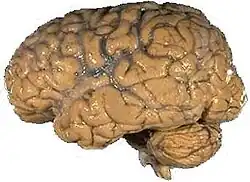

Encéfalo humano | |